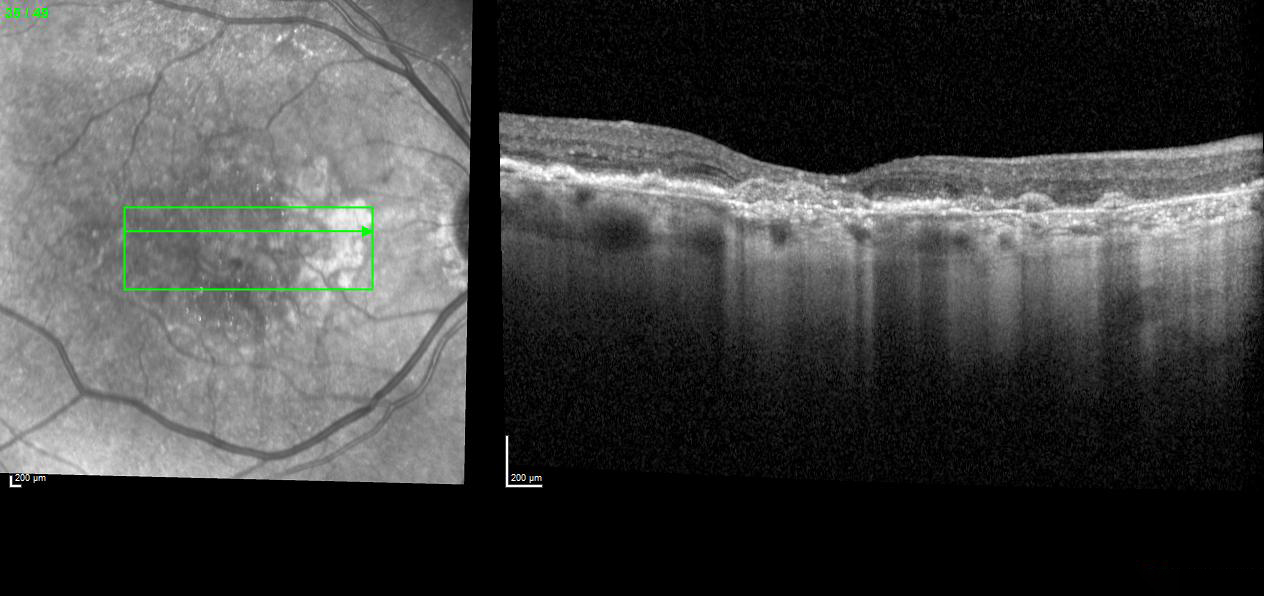

Actual Review: (Referral sent to Dr. Lee Feb 4, 2025) Agree with your assessment. This patient has wet age-related macular degeneration in the left eye.

Fundus photos show drusen and geographic atrophy. OCT and OCT angiography confirms  choroidal neovascularization. The patient needs treatment with anti-VEGF.